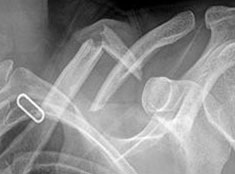

Clavicle fractures are diagnosed by taking a history, performing a physical examination and ordering imaging studies (X-ray ).

During this surgical procedure, the broken bone-ends are aligned into their normal position and screws in metal plates are used to hold the bone fragments in place.

These plates and screws are usually left in the bone. If they cause any irritation, they can be removed after fracture healing is complete.